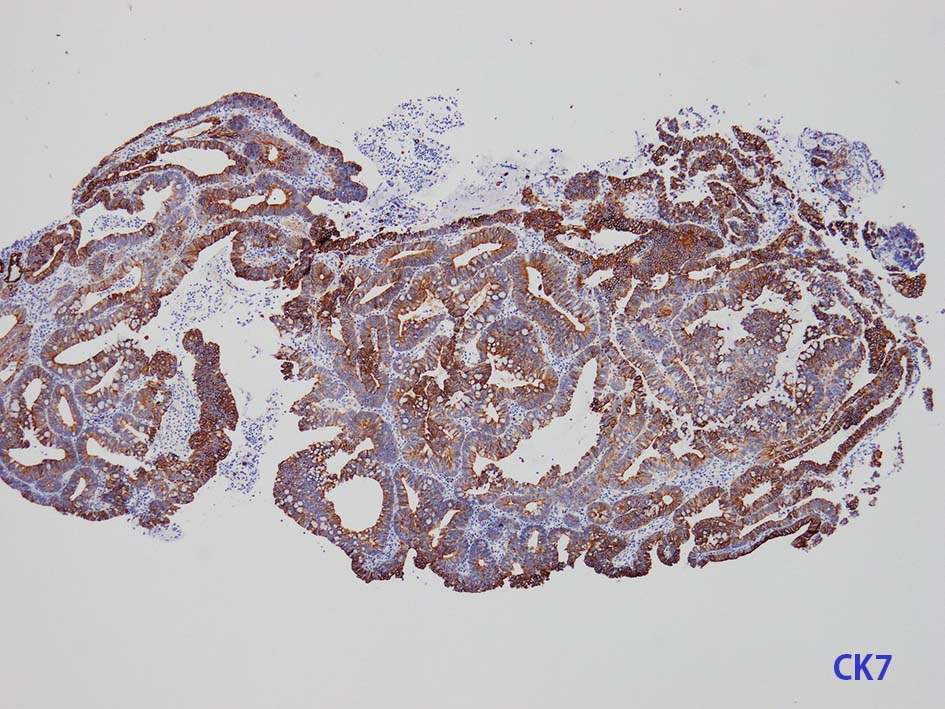

膀胱原発腺癌の診断に, サイトケラチン7および20、34βE12、トロンボモジュリン、CDX2およびβカテニンなどの免疫組織化学的パネルが提案されている。しかし他の原発部位に発生する腺癌と組織像だけでなく免疫組織化学的特徴が重複している. 原発性腺癌と転移性腺癌では予後や治療法が大きく異なるため, 鑑別診断において膀胱腺癌の診断を下す際には、臨床的、画像的、組織的、および免疫組織化学的な相関を注意深く確認する必要がある。

腸管型の腺癌。大腸の高分化腺癌と組織学的に区別は難しい.

mark-g.gif 免疫染色